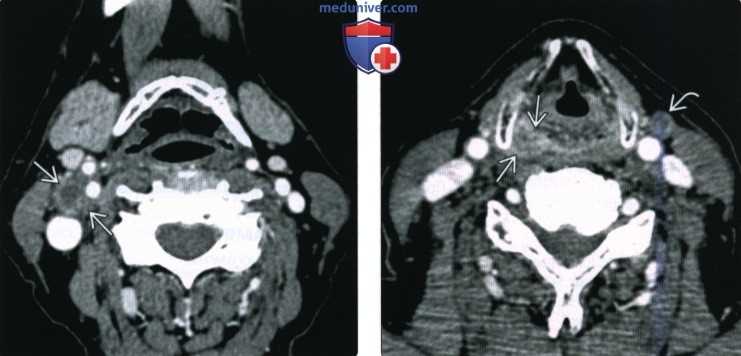

Кросс-секционные методы визуализации, такие как компьютерная или магнитно-резонансная томография, позволяют получить детальные изображения углублений и прилегающих тканей. Эти исследования помогают обнаружить опухолевые образования или воспалительные процессы.